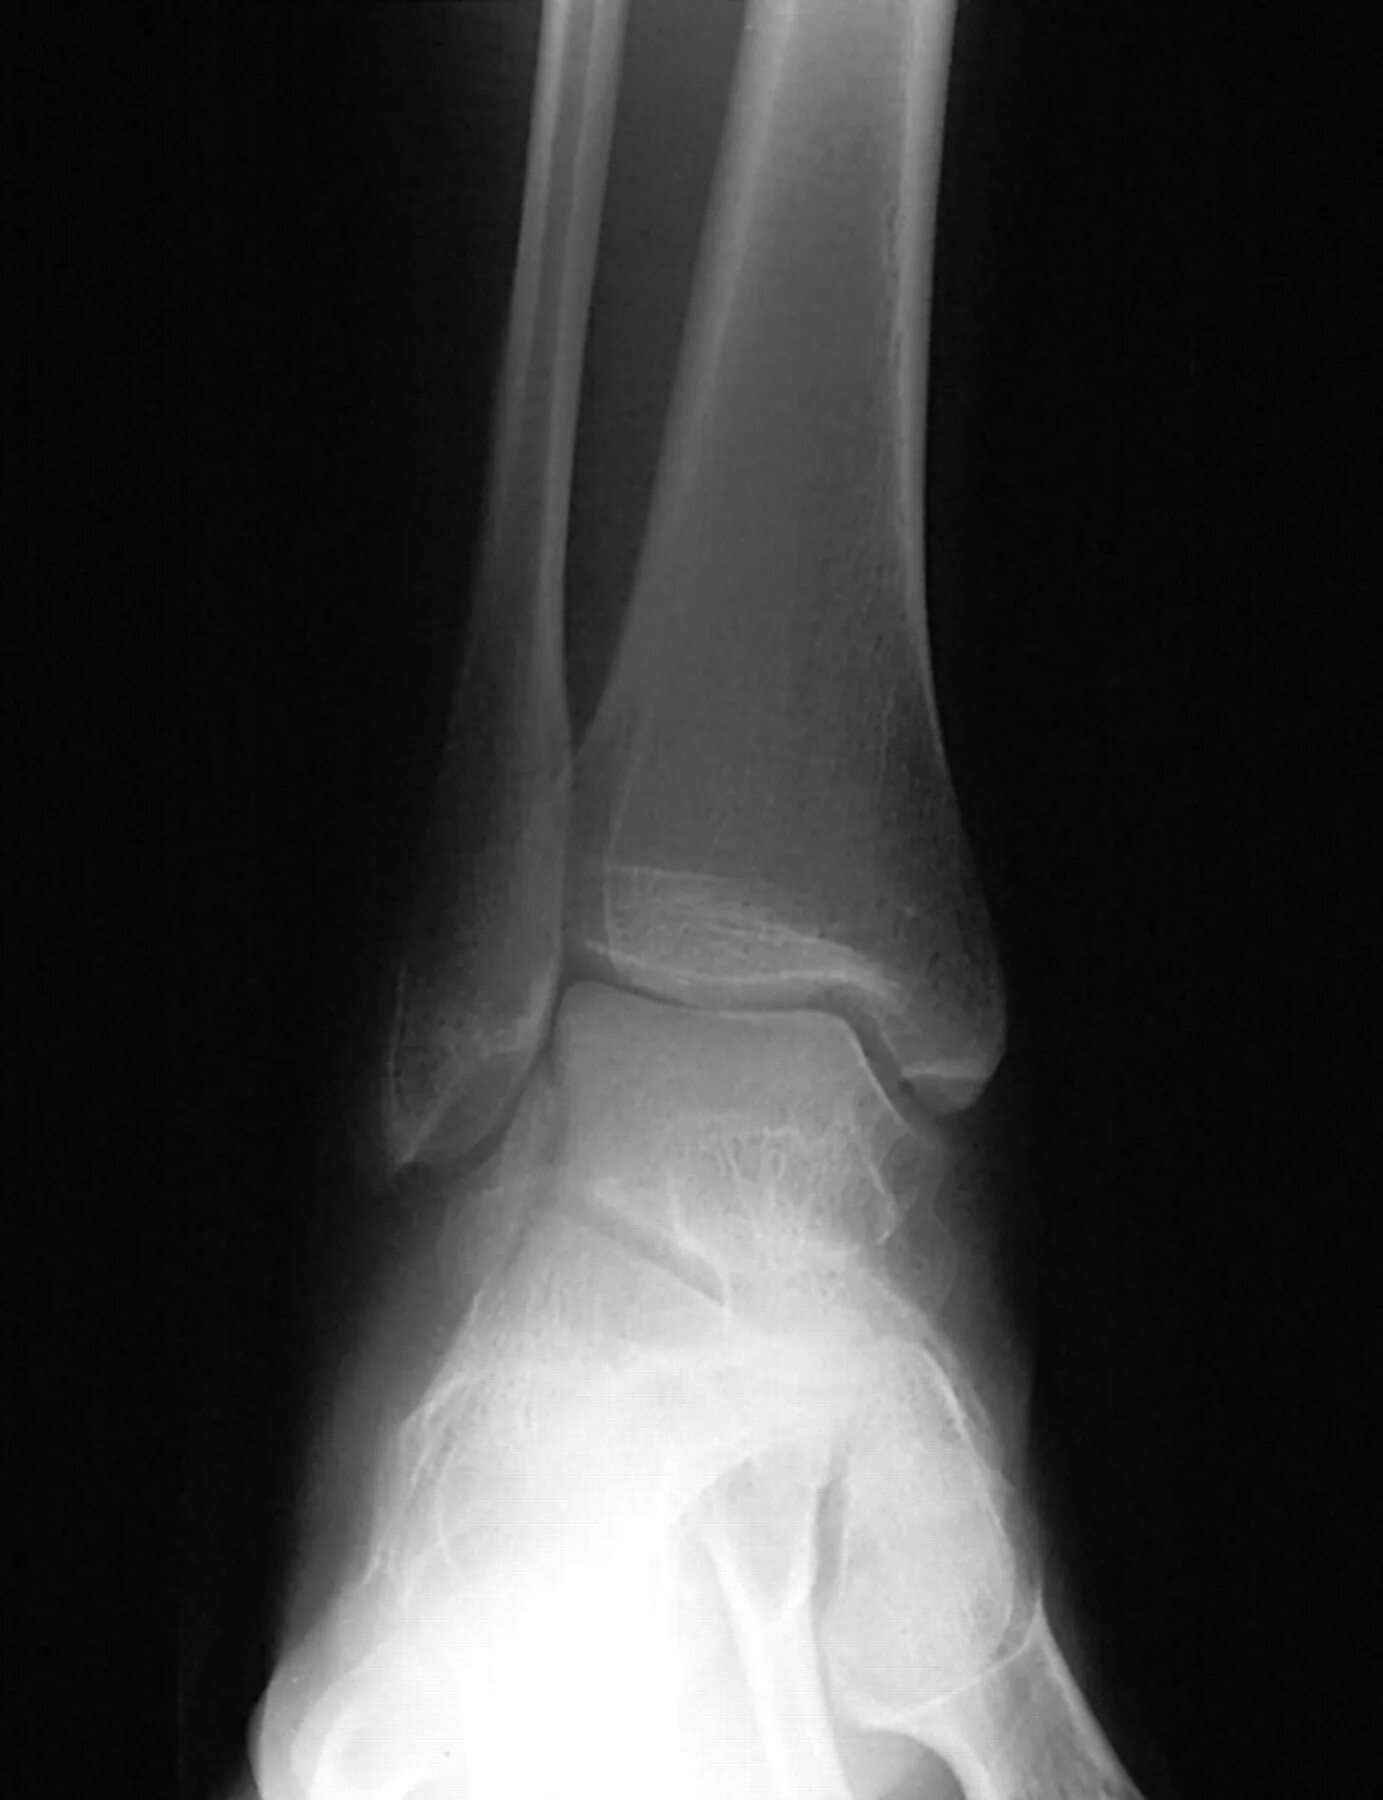

Чтоб кости быстро срослись